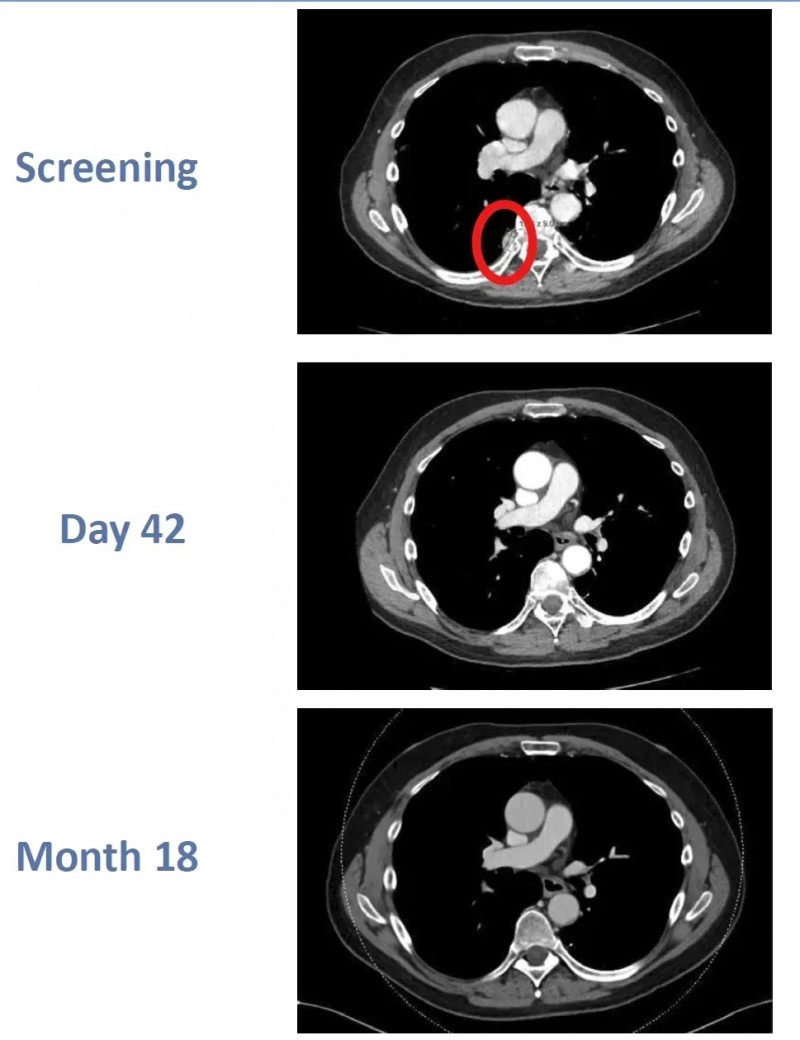

尤为值得关注的是,其中一例完全缓解的患者在治疗后未接受任何其他抗癌治疗,且3年后仍保持无病状态。

该患者是一位64岁男性,确诊ccRCC后接受阿替珠单抗联合卡博替尼治疗,病情仍复发并转移至肺部、胸膜,随后入组该临床试验。接受CTX130治疗后,患者先达到部分缓解(PR),治疗第3个月便实现完全缓解(CR),且这一状态持续稳定,至治疗第18个月复查时,完全缓解状态仍未改变。

▲图源“BMJ”,版权归原作者所有,如无意中侵犯了知识产权,请联系我们删除